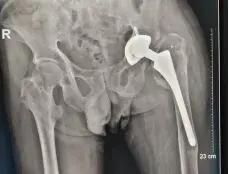

拔牙前和拔牙后影像对比

一切准备就绪,关节外科李炜明主任、吴星副主任、李章来副主任、康荣彬主治医师专家团队为陈依伯实施手术。医生切开患处,便看到大量脓液流出来。陈依伯的臀大肌之间还存在大量脓细胞,组织遭受破坏,坐骨神经也被脓液侵蚀,甚至股骨大粗隆及小粗隆的骨质也遭受破坏出现骨折,周围伴有异物巨噬反应。

面对复杂的病情,专家团队凭借精湛的医术和丰富的经验,有条不紊地拔除旧假体,彻底清创不放过任何一处感染,精准装入新假体进行调整。在麻醉科一路保驾护航下,手术历时2个半小时顺利完成。